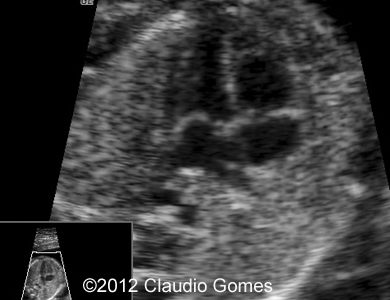

Image 1: At 21 weeks, persistent right umbilical vein ( arrow) next to gallbladder (*)

f1

Image 2: Routine transverse view of the abdomen and thorax showing a vessel posterior and to the right of the aorta (Azygos vein).

Fig3